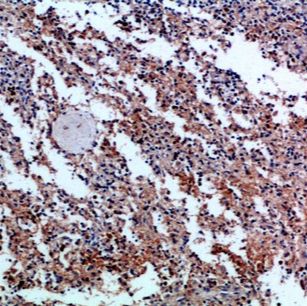

Product Image |

|

| IHC | 1/50-1/100 |